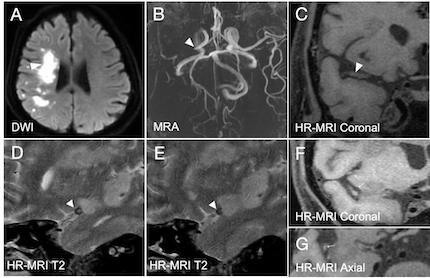

Abstract Body: Background and purpose: Deep tiny flow voids (DTFVs) are a specific type of collaterals surrounding chronic steno-occlusive middle cerebral artery (MCA), which can be identified on high-resolution magnetic resonance imaging (HR-MRI). This study aimed to investigate the presence of DTFVs in patients with acute MCA occlusion and their relevance to clinical outcomes.

Results: One hundred and twenty-three patients with acute MCA occlusion were included. The median age was 61 years (interquartile range [IQR], 51-67 years), and 73.73% of the patients were male. The median time from symptom onset to imaging was 44 hours (IQR, 25-67 hours). Sixty-six patients (53.66%) exhibited DTFVs on HR-MRI. Lower baseline NIHSS scores (4.5 [2-8] vs. 10 [4-14]) and smaller infarct volumes (5.76 [2.79-15.34] cm3 vs. 19.01 [7.16-83.59] cm3) were observed in patients with DTFVs compared to those without. Both multivariable logistic regression (odds ratio [OR]: 6.22, 95% confidence interval [CI]: 1.82 to 21.29, p = 0.004) and linear regression analysis (β: -0.60, 95% CI: -1.06 to -0.14, p = 0.012) indicated that patients with DTFVs exhibited better 90-day functional outcomes. The mediating effect analysis showed that the effect of DTFV on 90-day mRS scores was partially mediated by residual flow distal to MCA occlusion, with a proportion of 30.66% (95% CI: 8.97 to 69.29, p = 0.002).

Conclusions: In our study population, the presence of DTFVs was associated with a favorable outcome in patients with acute MCA occlusion, which may exert a protective effect partly by contributing to the formation of distal residual flow at the occlusion sites. Future studies are needed to investigate the potential of DTFVs in guiding individualized treatment strategies.